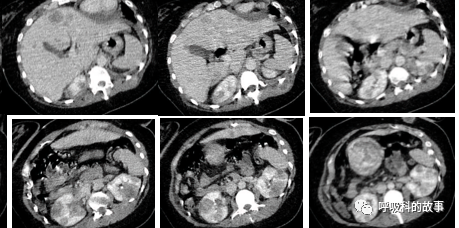

患者肝脏体积增大,里面密密麻麻分布着大小不一的结节,右侧膈肌明显抬高,使得右肺体积明显缩小;右肺门与肺动脉交界处有一个肿块(如下图):